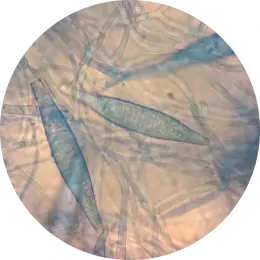

Badanie diagnostyczne w kierunku dermatofitów prowadzi do identyfikacji drobnoustrojów do gatunku. Właściwa identyfikacja jest niezbędna pod względem klinicznym i profilaktycznym. Pozwala ona na rozróżnienie zakażeń dermatofitowych od innych niegrzybiczych chorób jak np. łuszczyca, liszaj płaski paznokcia lub bielactwo paznokci oraz na odpowiednie dobranie leków przeciwgrzybiczych.

Fusarium spp